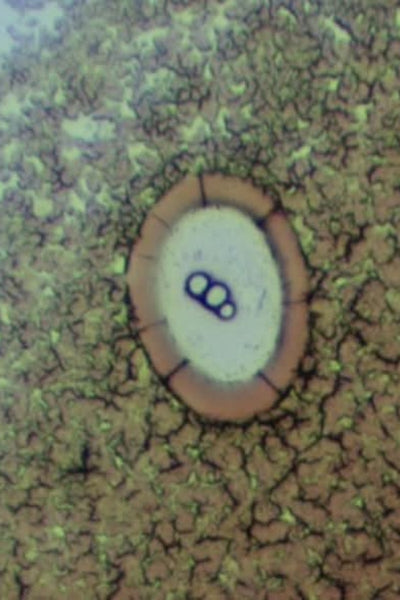

Live blood testing enables us to see your blood exactly as it behaves inside your body, giving a clear picture of your health at a cellular level.

Just one drop of blood is obtained from your fingertip and immediately examined under a high-powered microscope. The results are captured on camera so you can view your live blood—still interacting and moving—on screen.

The condition and quality of your red blood cells have a direct impact on your present and future health, with stress and disease visible in the live blood years before they manifest in the body.